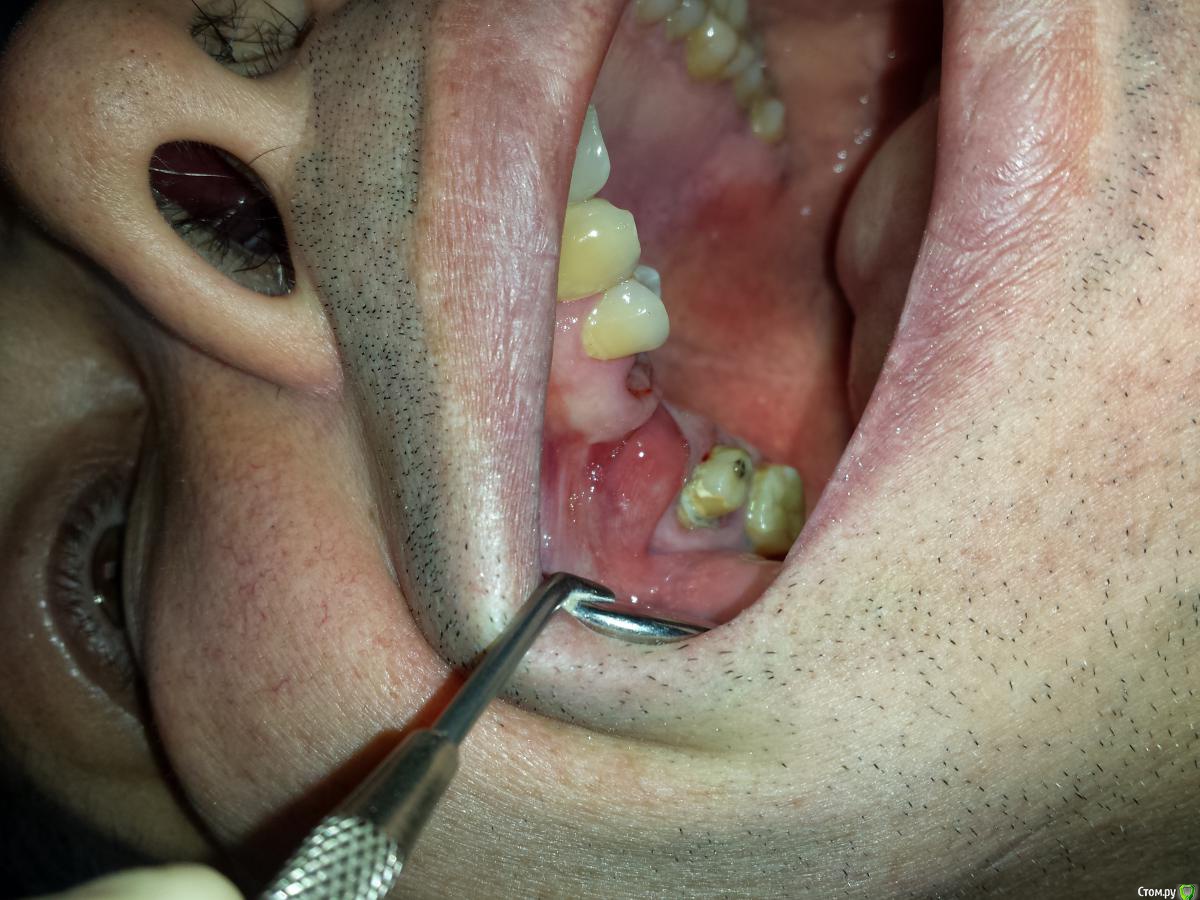

lonely_jack Опубликовано 3 декабря, 2014 Поделиться Опубликовано 3 декабря, 2014 Всем привет)))Образование на слизистой верхней челюсти, "мягкий мешочек"Со слов пациента появилось лет 20 назад, не болит, не беспокоит.У кого какие мысли? Если имплантировать в данной области, как с этой бякой быть? Ссылка на комментарий

Jangler Опубликовано 3 декабря, 2014 Поделиться Опубликовано 3 декабря, 2014 Это не образование а. состояние после пластики оас в области удаленого зуба. 2 Ссылка на комментарий

zubnojvrach Опубликовано 4 декабря, 2014 Поделиться Опубликовано 4 декабря, 2014 ситуация после пластики, можно апикально сместить лоскут для создания зоны кпд и преддверия полости рта но это на втором этапе имплантации Ссылка на комментарий

kriokov Опубликовано 4 декабря, 2014 Поделиться Опубликовано 4 декабря, 2014 ситуация после пластики, можно апикально сместить лоскут для создания зоны кпд и преддверия полости рта но это на втором этапе имплантацииТам кости нет вестибулярно‘ видно западение гребня, кт или оптг надо Ссылка на комментарий

kladoffka Опубликовано 4 декабря, 2014 Поделиться Опубликовано 4 декабря, 2014 Согласен, похожее бывает у нас в ЧЛХ после пластики соусться с гайморовой.+1 за снимок Ссылка на комментарий